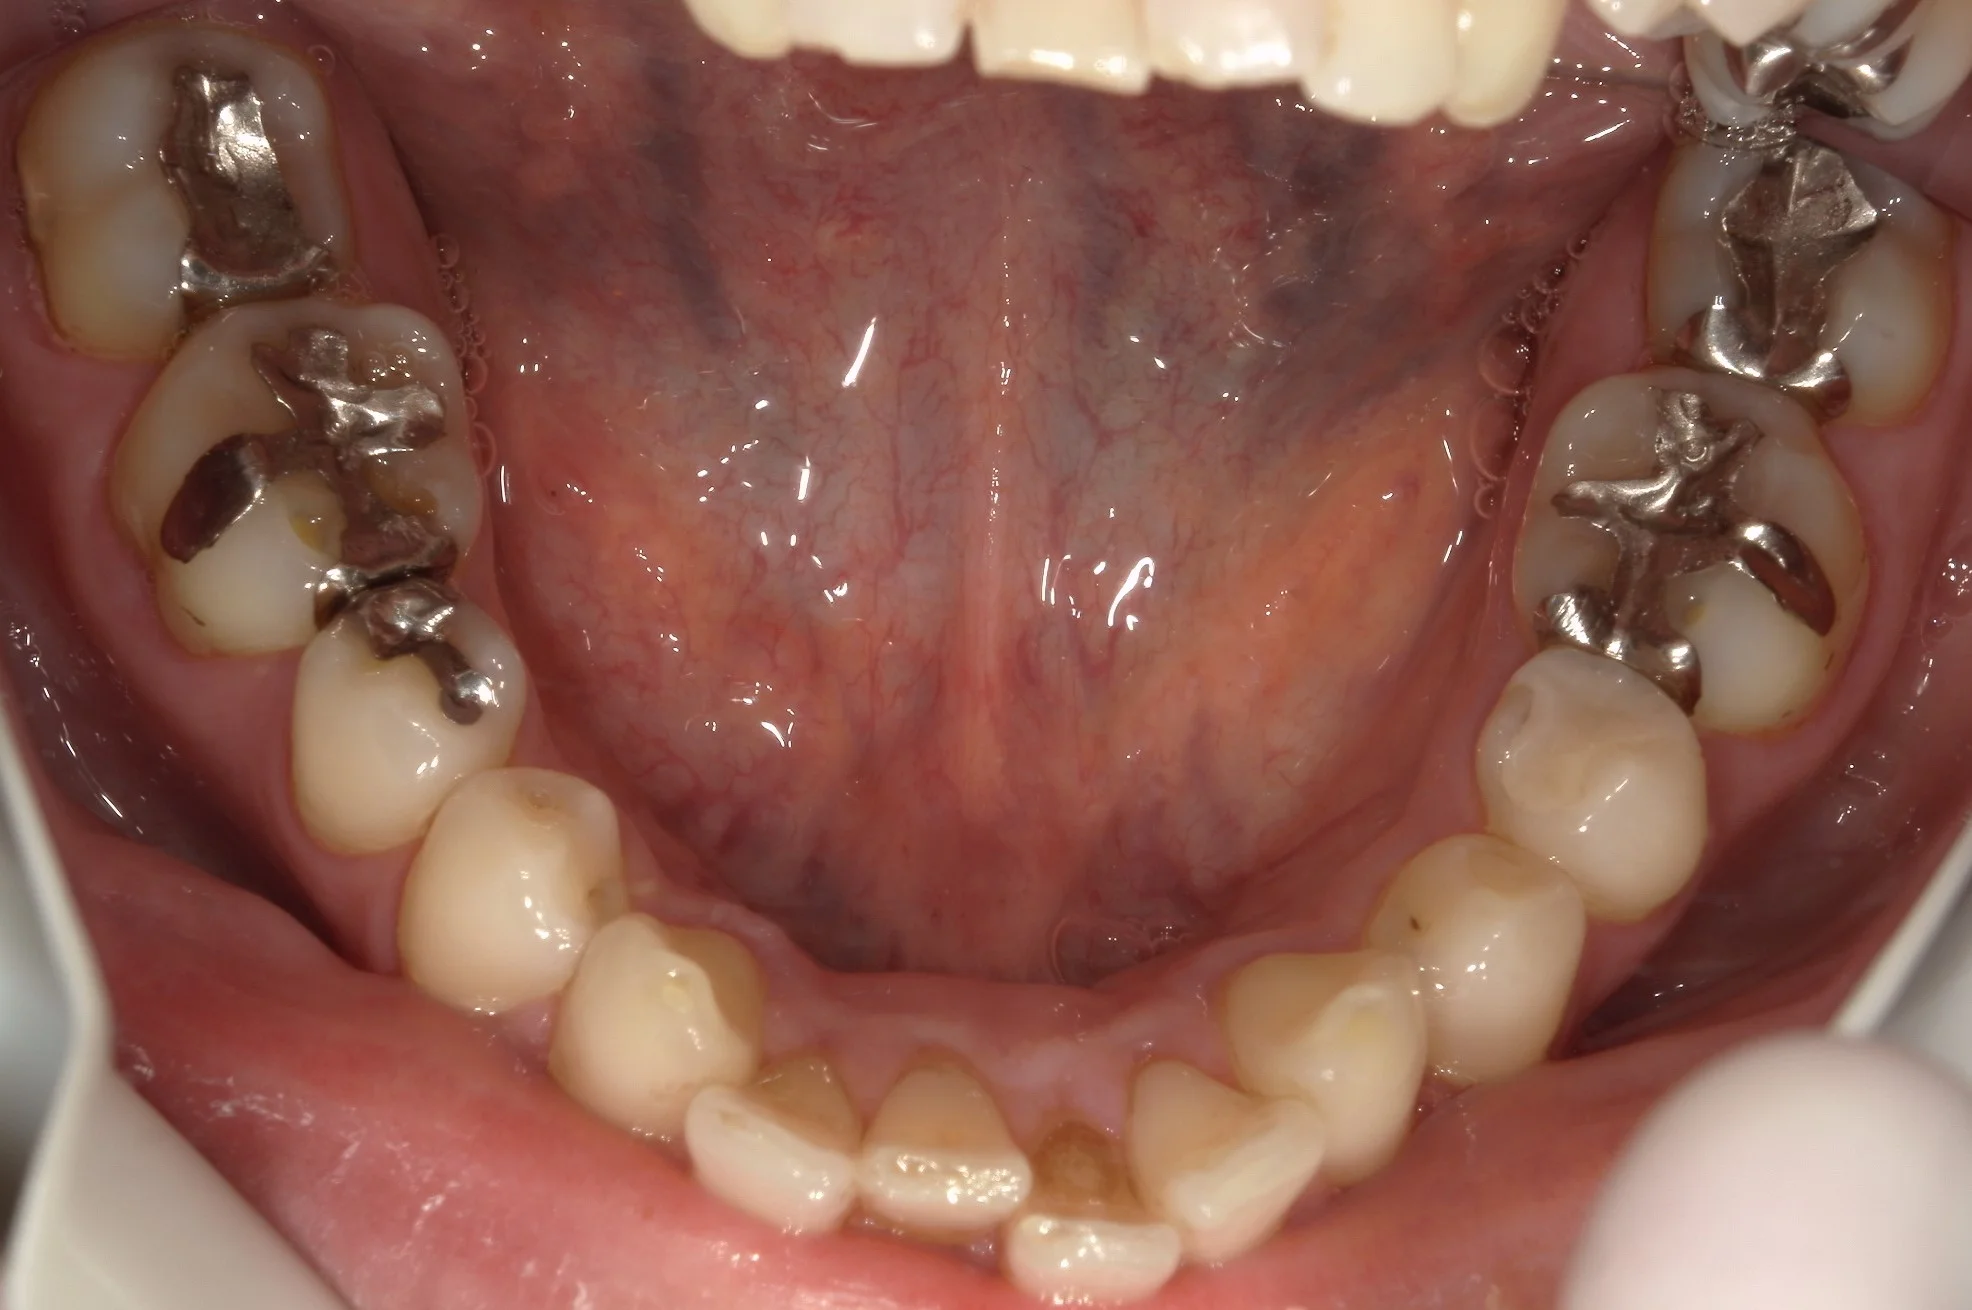

角度を変えて、咬む面からのみ撮影した術前術後がこちらになります。

術前

↓

術後

如何でしょうか?

歯の削れていた部分も綺麗に治り、自然な仕上がりになったかと思います。

エナメル質という表層部分が詰めるときに乾燥する影響で白っぽくなり、色が合っていないように見えますが・・・1週間もすれば色が戻り、違和感はなくなってくるかと思われます。

適合もしっかりと合わせているので、長く使っていただければ幸いですヽ(゚∀゚)ノ パッ☆